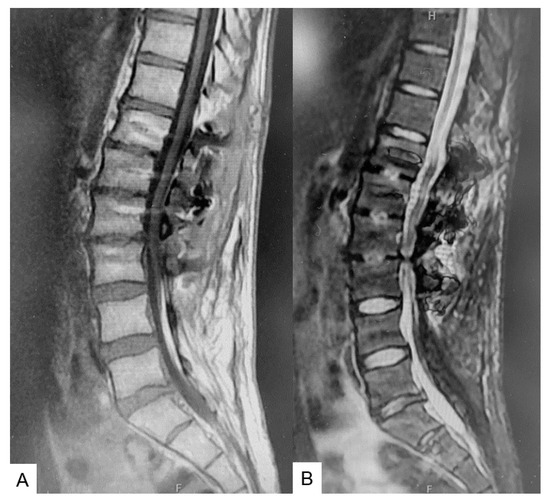

2.3. Preoperative Imaging

2.5. Postoperative Images